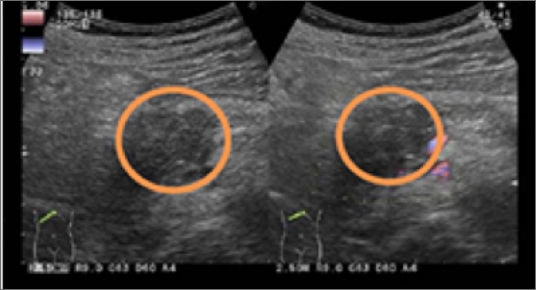

• 検査のイメージ

肝細胞癌